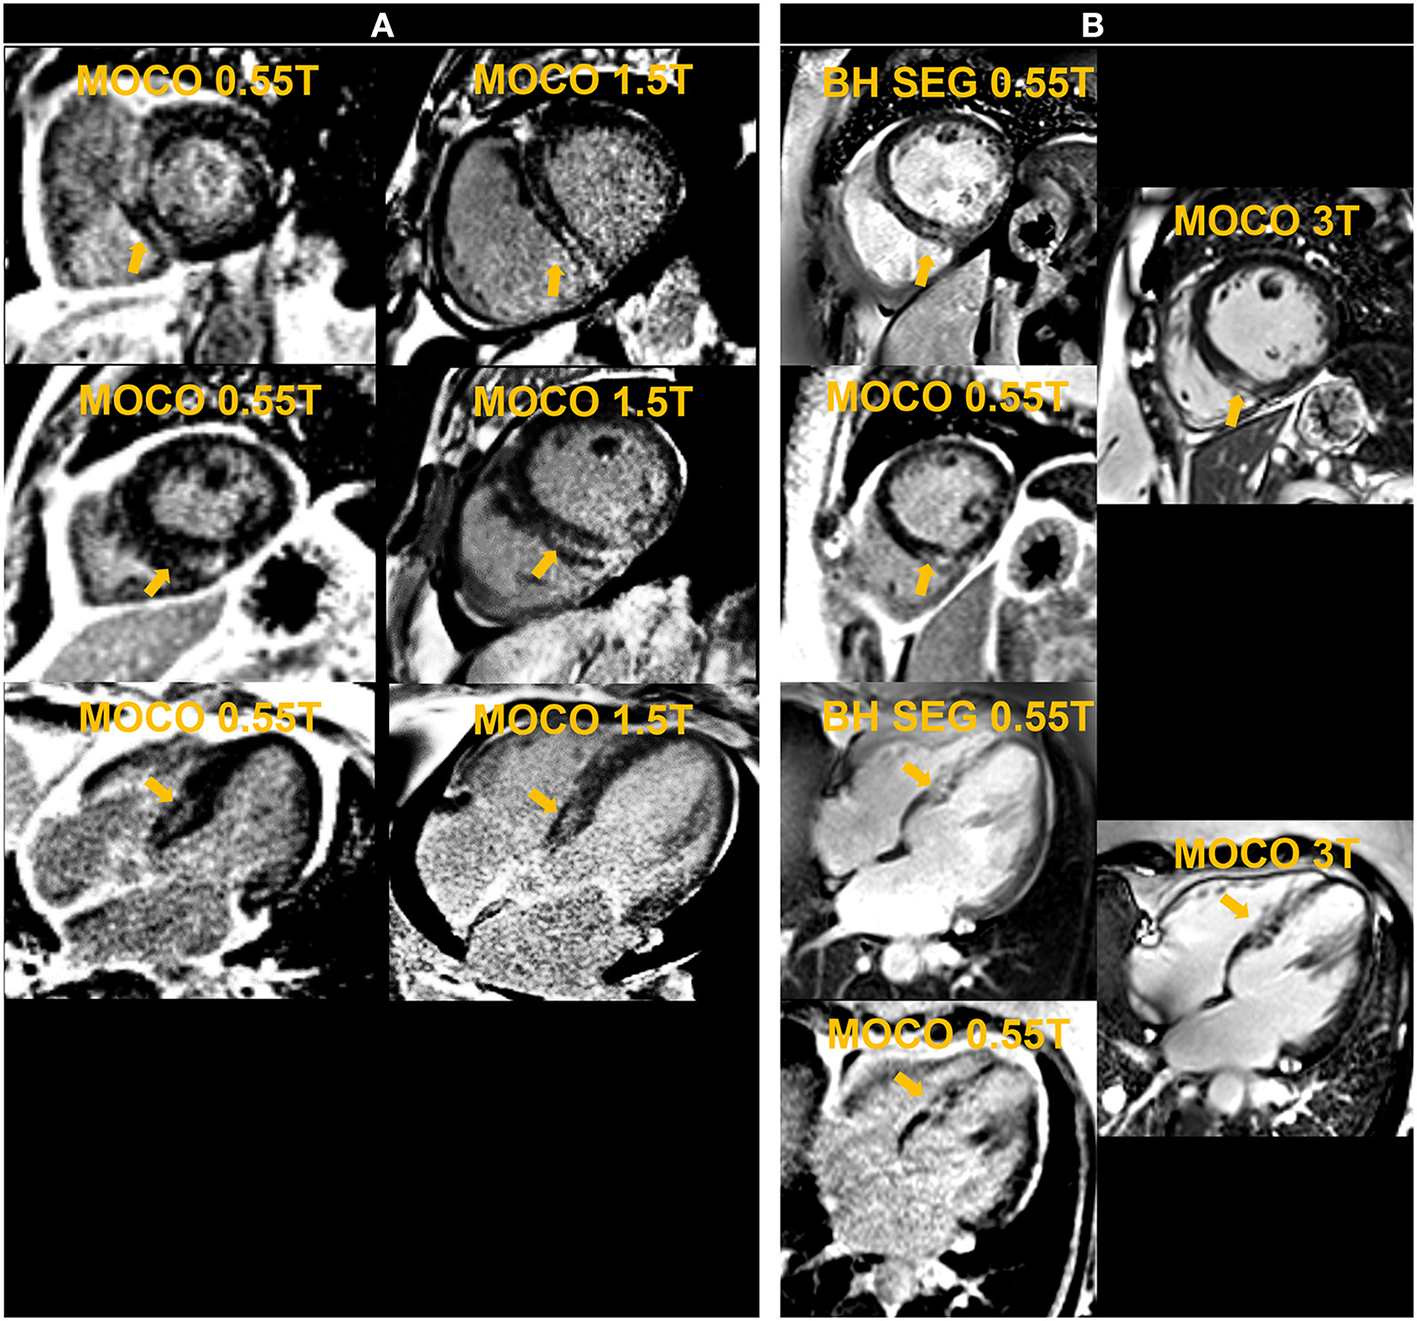

Figure 8

The left panel shows motion-corrected and averaged free-breathing single-shot late gadolinium enhancement images (MOCO LGE) in a patient [Patient (A)] demonstrating mid-wall non-ischemic fibrosis pattern at 0.55 T and 1.5 T. The right panel shows breath-held (BH) segmented (SEG) and MOCO LGE images acquired at 0.55 T in comparison to corresponding MOCO LGE images at 3 T in another individual [Patient (B)] and demonstrates infarct scar at the inferior septum.

For free-breathing LGE, twelve averages requiring 24 HB per slice were used to boost SNR, compared to the standard 8 averages employed in our 1.5 T and 3 T protocols. We observed failures of the motion correction algorithm, similar to what we observed in cardiac mapping, most likely due to the low SNR of the single-shot source images. This limited the benefits of increased averaging. The preliminary example images from animals and patients with positive LGE confirmed on 1.5 T and 3 T systems are promising. Additional assessments are warranted to correlate the extent of LGE to that depicted by 1.5 T and 3 T systems.